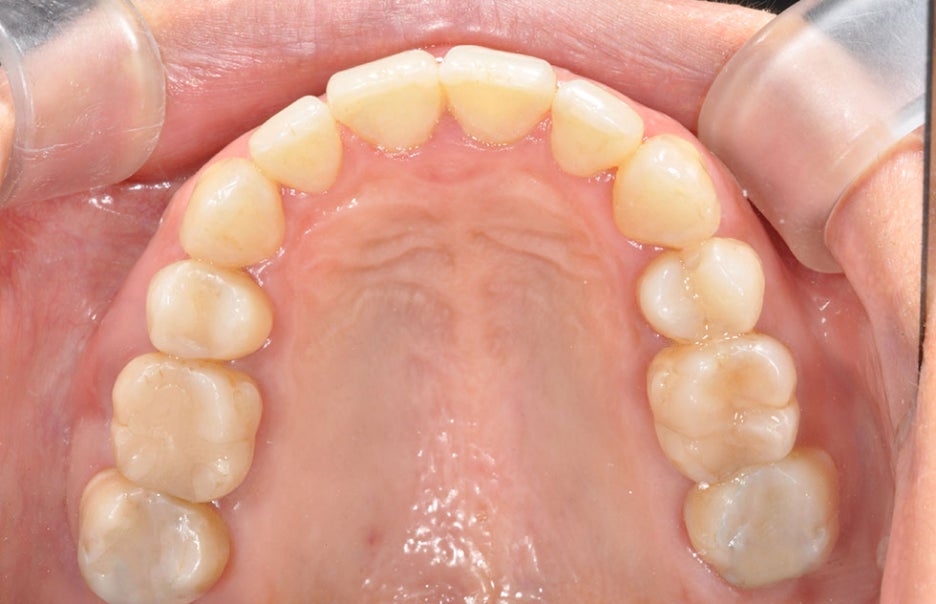

서울교정잘하는치과 뉴엔만의 장점

치아교정의 경우 기본적으로 메탈,

세라믹교정 모두 가능하며, 투명교정의 경우

지금 널리 쓰이는 재료와는 다른 형상기억

기능과 맞춤형으로 특허를 받은

투명 교정으로 진행합니다.

장치가 치아에 딱 맞는 정도와 교정력이

우수하며, 뜨거운 물에 넣으면 말랑해지고

차가워지면 교정장치 원래 모습으로

돌아가므로 망가질 염려가 없고 1~2주간

쓰는 교정 장치가 처음 교정력이

계속 유지가 되어 교정 효력이 좋습니다.

뜨거운 물에 넣었을 시 말랑해지는 특성이 있어

탈착이 용이하며 뜨거운 물에 소독도 가능하여

청결하게 관리할 수 있습니다.

저희 뉴엔에서 특허를 받아 3D 컴퓨터 분석으로

면밀하게 교정받아 볼 수 있으시기를 바랍니다.